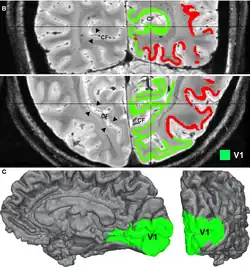

Adaptation is caused by the prolonged viewing of unchanging patterns. IOT in adaptation within the primary visual cortex has been explored. IOT as the ability to experience aftereffects in the eye that did not view the adapting pattern occurring in the primary visual cortex (V1) of cats. IOT may be mediated by callosal connections between the two hemispheres, and is not dependent on the conventional binocularity of neurons. The study attempted to provide the physiological evidence to the existence of IOT.[14]  There is also FMRI evidence that observed binocular visual interactions in the visual cortex in humans.[15]